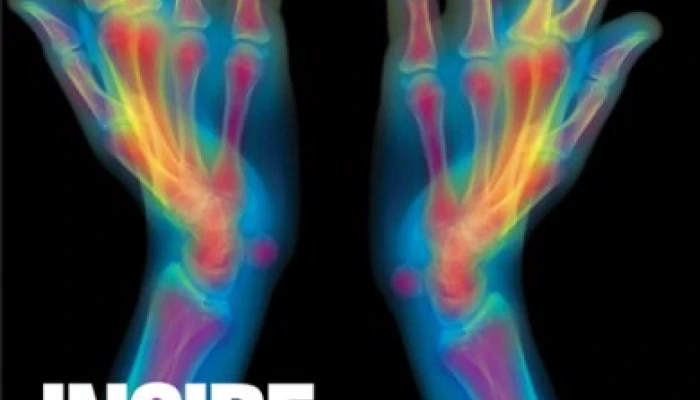

Inside the Body: Fantastic Images from Beneath the Skin

For those of us who spend our time thinking about, talking about, and arguing about biopolicy, this book issues a refreshing call to take a moment appreciating the complex magnificence of the human body.  From simple x-rays of the ankle to wonderfully detailed scanned electron micrographs of fallopian tubes, a full range of imaging techniques are demonstrated in this richly coloured gallery of the human body.  This collection of images, stripped of the sophisticated educational or diagnostic purposes that biomedical imaging so often bears, encourages readers – young or old, expert or lay – to look afresh at the bodies we inhabit.

The short introduction describes the various imaging techniques used in the book, and places many in historical context.  From the 17th century invention of the microscope, to the development of MRI and CT scans in the 1970s, one is reminded that the privilege of gazing inside the body is a cultural achievement.  For this reason, Inside the Body,  is not solely about the ‘natural’ body, seen in primordial glory.  The very colours of the images also pay testimony to the vibrant synergy that has been developed between body and culture, between scientific endeavour and artistry.  These pictures are emphatically cultural artefacts, a collaboration not just between technology and the natural body, but between a vast host of professions from research physicists and lab technicians, to medics and IT programmers.